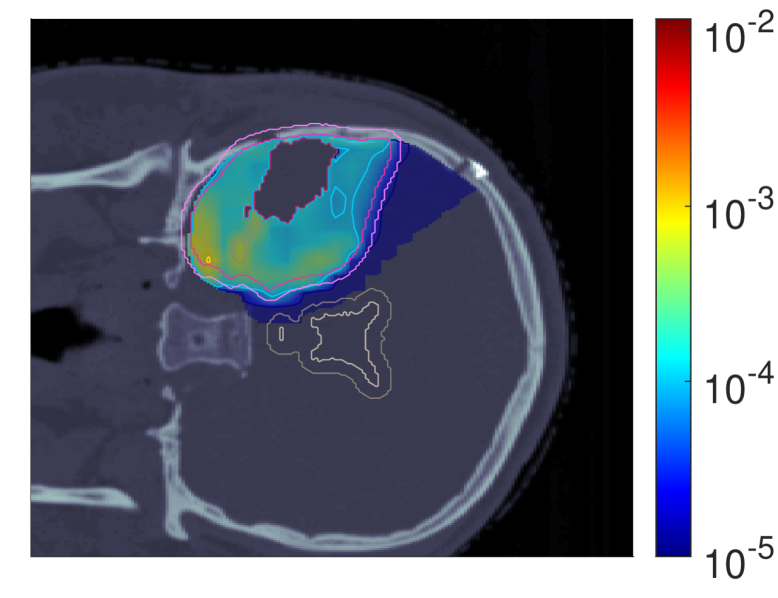

III.A.1 RBE-weighted fractional dose dRBE,fxd_{RBE,fx}

Figure 3 shows the slice images with the optimal dose distributions, where the POLO model-based objective functions are displayed vertically and the NTCP levels horizontally.

NTCP30 %NTCP\approx{$30\text{\,}\mathrm{\char 37\relax}$} NTCP20 %NTCP\approx{$20\text{\,}\mathrm{\char 37\relax}$} NTCP10 %NTCP\approx{$10\text{\,}\mathrm{\char 37\relax}$}

dRBE,fxd_{RBE,fx} (NTCPp)(NTCP_{p})

Refer to caption Refer to caption Refer to caption

dRBE,fxd_{RBE,fx} (LSEp~)(LSE_{\tilde{p}})

dRBE,fxd_{RBE,fx} (H~p)(\tilde{H}_{p})

dRBE,fxd_{RBE,fx} (H~p~)(\tilde{H}_{\tilde{p}})

Figure 3: Optimal slice images of the RBE-weighted fractional dose dRBE,fxd_{RBE,fx} (in Gy\mathrm{Gy}(RBE)) for NTCPpNTCP_{p}, LSEp~LSE_{\tilde{p}}, H~p\tilde{H}_{p} and H~p~\tilde{H}_{\tilde{p}} at different NTCP levels. The objective functions behave similarly in that dose is reduced to achieve a lower NTCP value. However, they differ in the strength of the dose reduction inside and the impact on the dose outside the target volume, particularly in the VS. NTCPpNTCP_{p} and H~p\tilde{H}_{p} show comparable dose results, while LSEp~LSE_{\tilde{p}} and H~p~\tilde{H}_{\tilde{p}} more aggressively eliminate dose in the target volume.

We observe intra-functional similarities of the objectives from a reduction of the dose values with decreasing NTCP level, especially in the overlapping regions to the VS, but also within the target volumes. NTCPpNTCP_{p} manages to reduce the risk estimate by almost 26 %26\text{\,}\mathrm{\char 37\relax} compared to the baseline plan without affecting target coverage (ΔPTVd95RBE,fx0.03\Delta_{\text{PTV}}\text{d95}_{RBE,fx}\approx{0.03}, ΔGTVd95RBE,fx0.001\Delta_{\text{GTV}}\text{d95}_{RBE,fx}\approx{0.001}), which can be attributed to the dose contraction away from the VS. This is even more pronounced when lowering the NTCP level to 10 %10\text{\,}\mathrm{\char 37\relax}, but is then accompanied by a loss in target coverage (ΔPTVd95RBE,fx0.07\Delta_{\text{PTV}}\text{d95}_{RBE,fx}\approx{0.07}, ΔGTVd95RBE,fx0.02\Delta_{\text{GTV}}\text{d95}_{RBE,fx}\approx{0.02}).

From an inter-functional perspective H~p\tilde{H}_{p} seems to behave very similarly, with only minor deviations in the dose slice. In contrast, we find that LSEp~LSE_{\tilde{p}} and H~p~\tilde{H}_{\tilde{p}} modulate the dose more strongly, with local inhomogeneities already at an NTCP level of 30 %30\text{\,}\mathrm{\char 37\relax}. Here, LSEp~LSE_{\tilde{p}} only marginally reduces the dose in the upper part of the VS but restricts the dose exposure in the target volume (ΔPTVd95RBE,fx0.26\Delta_{\text{PTV}}\text{d95}_{RBE,fx}\approx{0.26}, ΔGTVd95RBE,fx0.1\Delta_{\text{GTV}}\text{d95}_{RBE,fx}\approx{0.1}). Even more, target coverage breaks down at an NTCP level of 10 %10\text{\,}\mathrm{\char 37\relax} (ΔPTVd95RBE,fx0.51\Delta_{\text{PTV}}\text{d95}_{RBE,fx}\approx{0.51}, ΔGTVd95RBE,fx0.24\Delta_{\text{GTV}}\text{d95}_{RBE,fx}\approx{0.24}). One reason could be the focus of LSEp~LSE_{\tilde{p}} on maximum points, causing a “notch” in the high dose region around the overlap of CTV/PTV and VS at an NTCP level of 20 %20\text{\,}\mathrm{\char 37\relax}.

H~p~\tilde{H}_{\tilde{p}}, on the other hand, results in an immediate dose contraction, with higher concentration on the GTV with lower NTCP level. Similar to LSEp~LSE_{\tilde{p}}, target coverage is drastically affected at 10 %10\text{\,}\mathrm{\char 37\relax} NTCP (ΔPTVd95RBE,fx0.71\Delta_{\text{PTV}}\text{d95}_{RBE,fx}\approx{0.71}, ΔGTVd95RBE,fx0.22\Delta_{\text{GTV}}\text{d95}_{RBE,fx}\approx{0.22}), which may be due to the increased scale of the function values and gradients of the linearly reformulated POLO model and therefore the higher impact of LSEp~LSE_{\tilde{p}} and H~p~\tilde{H}_{\tilde{p}} on the plan.

Above results are underlined by Figure 4 which displays the corresponding dose-volume histograms (DVHs) for the volumes of interest (VOIs) to allow for a global analysis of the dose distributions and their progression.